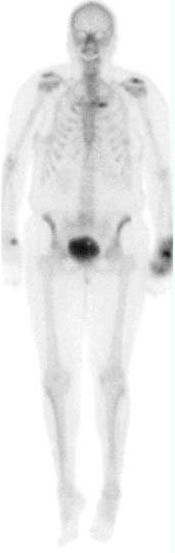

PET scan with extravasation of F18FDG in the right upper arm. In the case of PET imaging the infiltration of the dose results in invalid standard uptake value (SUV) which is determined by the exact patient dose (Pre-calibration - post-calibration) and the patient weight. If the patient dose is made inaccurate by the infiltrated dose the SUV becomes invlaid. The scan however may still be diagnostic if enough of the radiopharmaceutical has been properly delivered. The small dot of activity in the right shoulder may represent a lymph node due to the infiltration.

This patient was re-scanned with the area of extravasation out of the field of view and determined to be of diagnostic value.